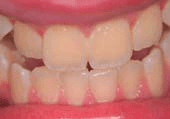

Figures 1 and 2 show cases of mild dental fluorosis (pictures provided by Dr Wendell Evans and Dr Ikreet Bal, the University of Sydney).

Figure 1: Very mild dental fluorosis along the lower edge of the upper front teeth